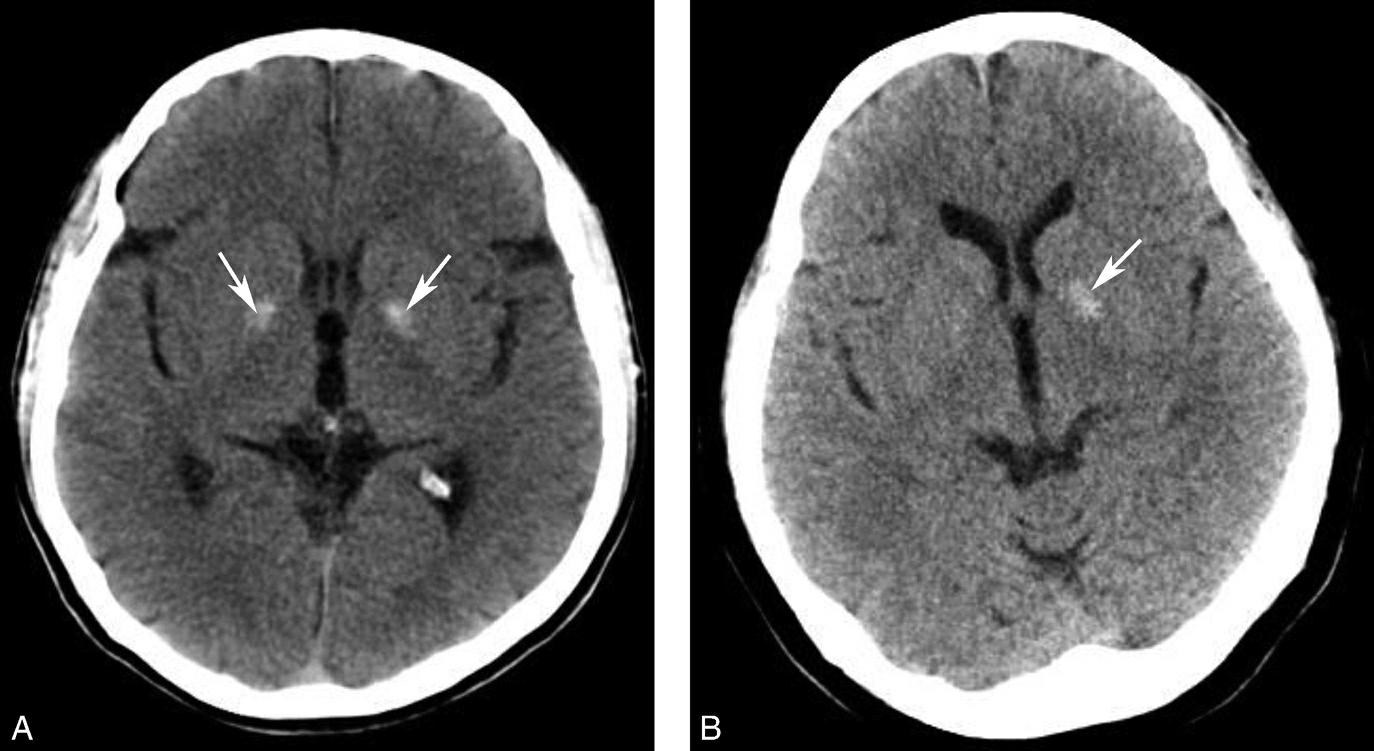

图1-2-14 静脉窦增宽、密度升高(静脉窦血栓)

男,47岁,头痛2周,意识模糊2天,无头颅外伤史。A.CT平扫示双侧横窦增宽、密度增高(黑箭),提示静脉窦血栓;B.MRI T 1 WI提示双侧乙状窦、横窦血栓形成(白箭)